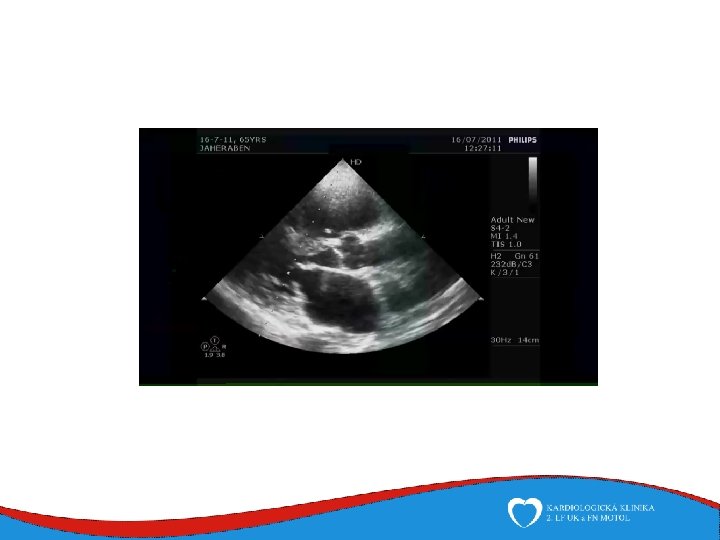

Echocardiography • • • Mainstay of valve disease diagnosis and follow-up Allows real-time measurement of chamber and wall diameters, ejection fraction assessment and functional valve evaluation Easily avaiable and repeated Essential in acute valve disease diagnosis No radiation harm Trans-esophageal echocardiography avaiable for patients with poor transthoracic sonographic window